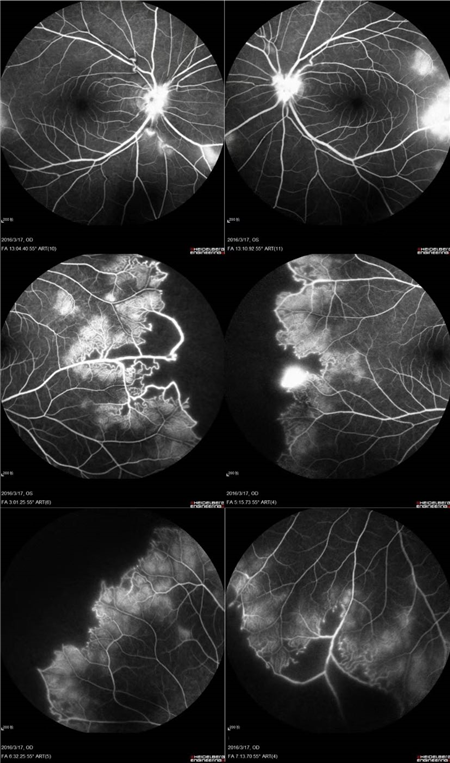

特发性视网膜血管炎、动脉瘤和视神经视网膜炎综合征(Idiopathic Retinal Vasculitis, Aneurysm, and Neuroretinitis syndrome,简称IRVAN综合征)是一种病因不明的较为少见的视网膜血管炎性疾病,此病症常在30-40岁发病且多为女性发病。在发病的前期,如果进行及时有效的治疗干预,预后效果多数较好。但一拖再拖,错过最好的治疗时间,可引起严重的并发症。在这里提醒大家,一定要密切关注自己眼部突发情况的出现,警惕眼前突然发生黑影飘动,视力下降的情况,尽早就医。

经过详细的眼底检查后,患者被诊断为IRVAN综合征引起的右眼黄斑裂孔,张风院长带领医生团队为患者施局右眼玻璃体切除+剥膜+眼内光凝+气液交换手术,经过半个月的恢复,患者右眼术后视力由术前0.3-达到0.6-的状态,且裂孔呈逐渐闭合状态。

视盘附近的动脉和动脉分叉处出现瘤样动脉扩张,视盘充血,边界不清,引起视盘周围视网膜内硬性渗出;视盘周可有少量放射状出血。

静脉不规则扩张和血管鞘膜,周边部小血管广泛闭塞,交界处毛细血管扩张和异常吻合。

严重者可发生从周边到黄斑的血管闭塞和缺血、玻血、新生血管性青光眼,最终视神经萎缩。